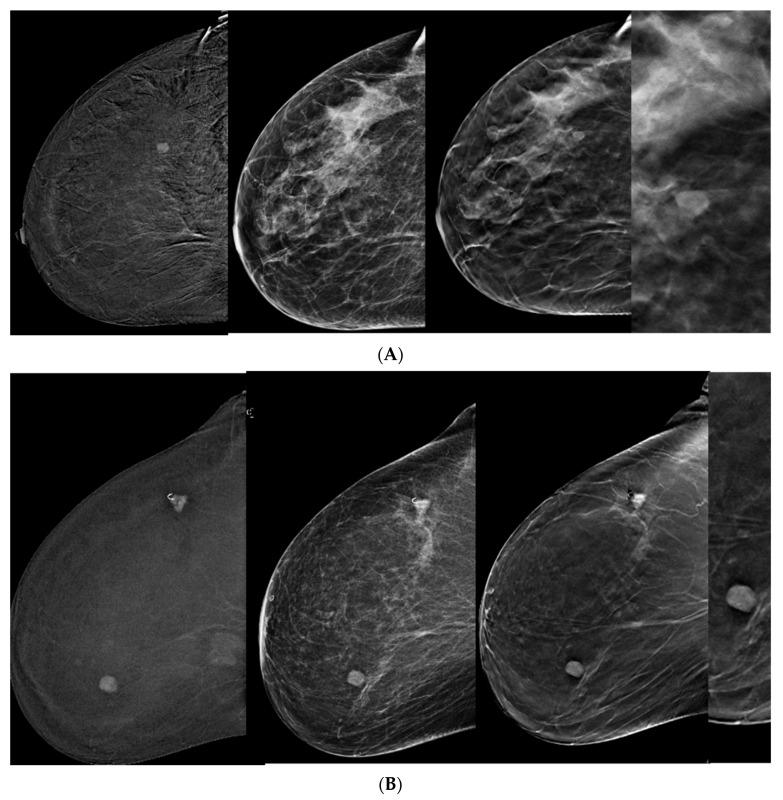

BIRADS scores of CEM-detected lesions were upgraded toward the lesion's pathology with the addition of DBT ( > 0.0001), overall and for each reader. The difference in BIRADS scores before and after the addition of DBT was more significant for readers who were less experienced. The reason for changes in the BIRADS score was better lesion margin visibility. The main BIRADS descriptors applied in the malignant lesions were spiculations, calcifications, architectural distortion, and sharp or obscured margins.

与 CEM 检出病变的 BIRADS 评分相比,添加 DBT 后(>0.0001),总体和每位读者的评分均升高。对于经验较少的读者,添加 DBT 前后 BIRADS 评分的差异更显著。BIRADS 评分变化的原因是更好地显示病变边界。在恶性病变中应用的主要 BIRADS 描述符是分叶状、钙化、结构扭曲和锐利或模糊的边界。